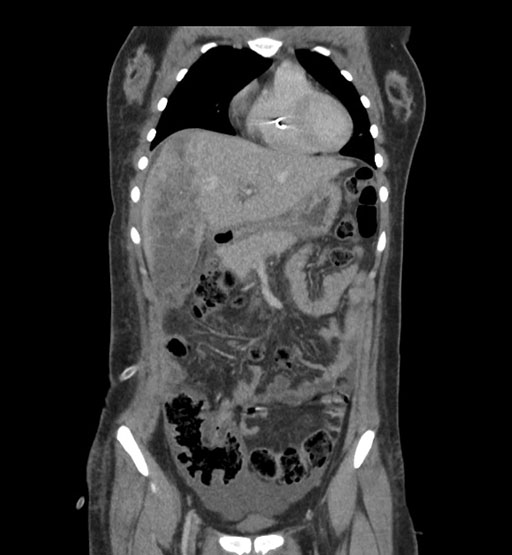

Axial Venous